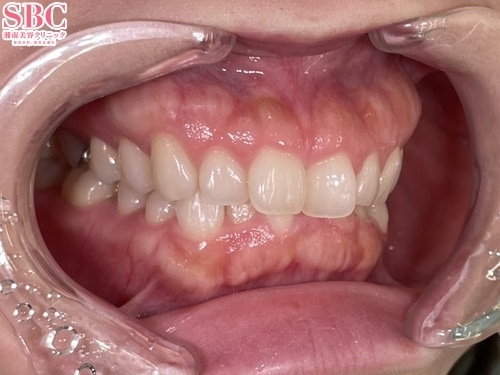

No.340185【美容歯科】【れいな先生】ガミースマイルも!バッカルコリドーも!DRれいなならここまで改善します☆【マウスピース矯正】

全体的に整えたいとのご希望

施術後9ヶ月後

歯のラインが整い笑顔が美しく大変身!

こちらの症例はインビザライン・モデレート両顎の症例になります(親知らずのみ抜歯)

全体的な歯のずれを整え、ラインを揃えました

揃ったことで、上の歯茎が見えにくくなり、ガミースマイルが改善。

また、内向きに倒れた歯を起こしバッカルコリドーの幅を小さく見せることで笑顔が格段に綺麗になりました☆